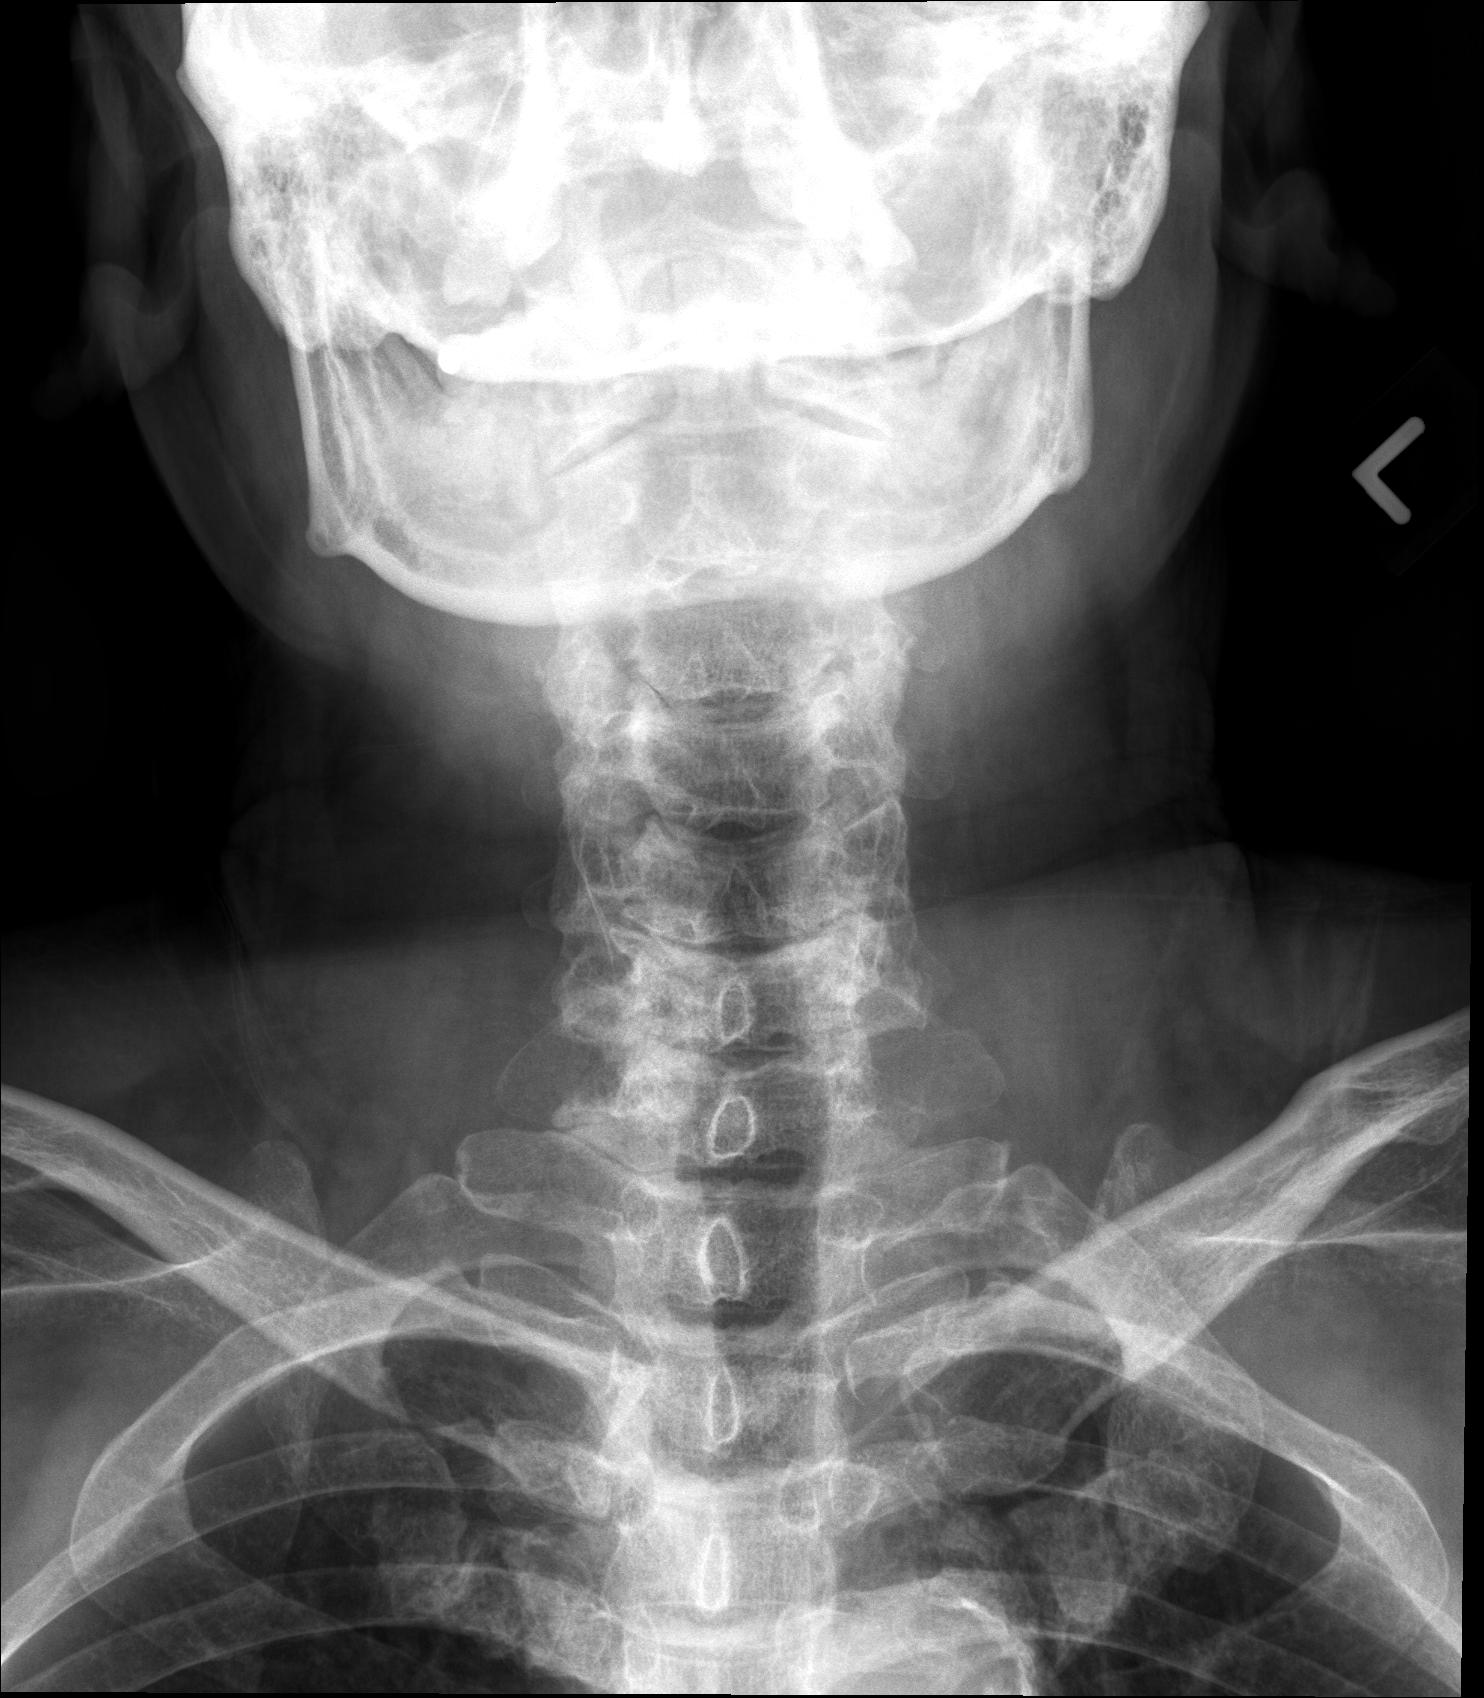

| Study | ID | Date | Accession # | Thumbnails | Report | XR ELBOW, AP & LAT, LEFT | 2766356 | 08/21/2019 | 2766356 | ... | MR WHOLE SPINE (FULL STUDY) | 32376 | 08/23/2019 | 2766095 | ... | XR CERVICAL SPINE, AP & LATERAL | 2765876 | 08/20/2019 | 2765876 |